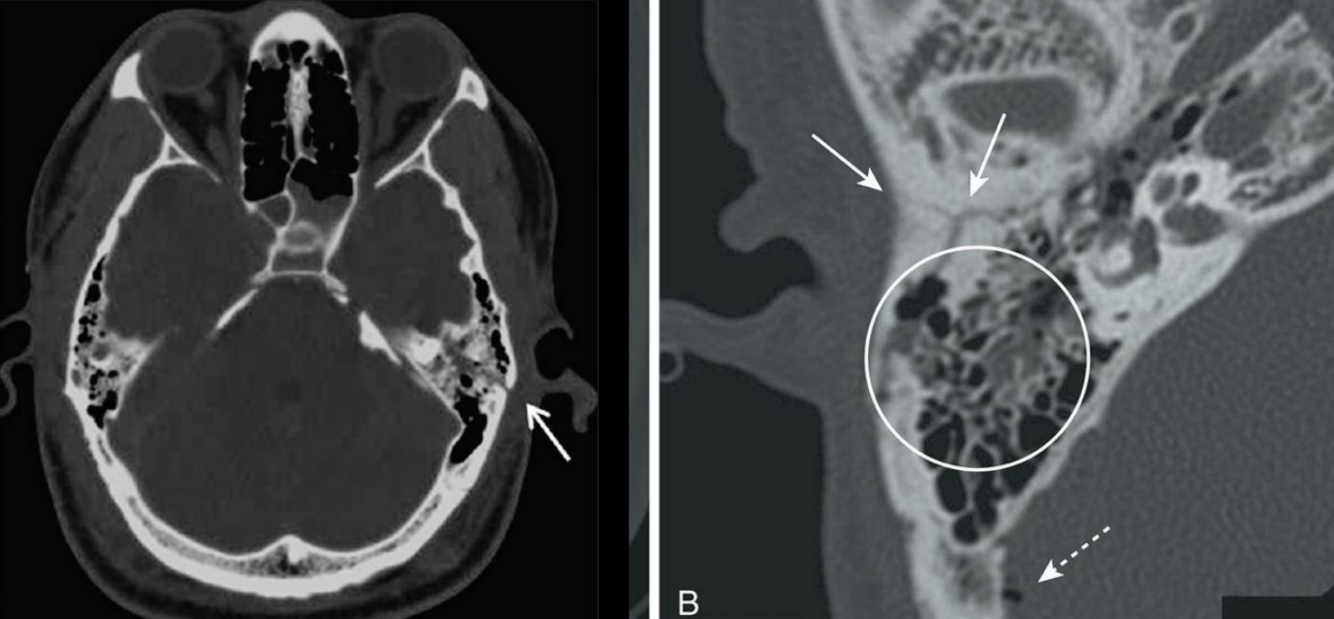

¿Qué fracturas se detectan solo por TC?

Fx de base de cráneo

Signos indirectos de fractura de base en TC

Sangre en seno esfenoidal, celdillas mastoideas, neumoencéfalo

Rino/oto raquia/ragia